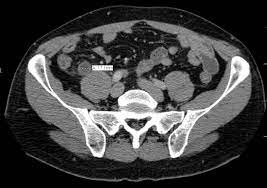

4. 복부 초음파: 복부 초음파 검사는 충수 부위의 염증 또는 다른 구조적인 이상을 확인하는 데 도움이 됩니다.

5. 컴퓨터 단층 촬영(CT 스캔): CT 스캔은 소장 및 충수 부위의 상세한 영상을 제공하므로 충수염 진단에 유용합니다.